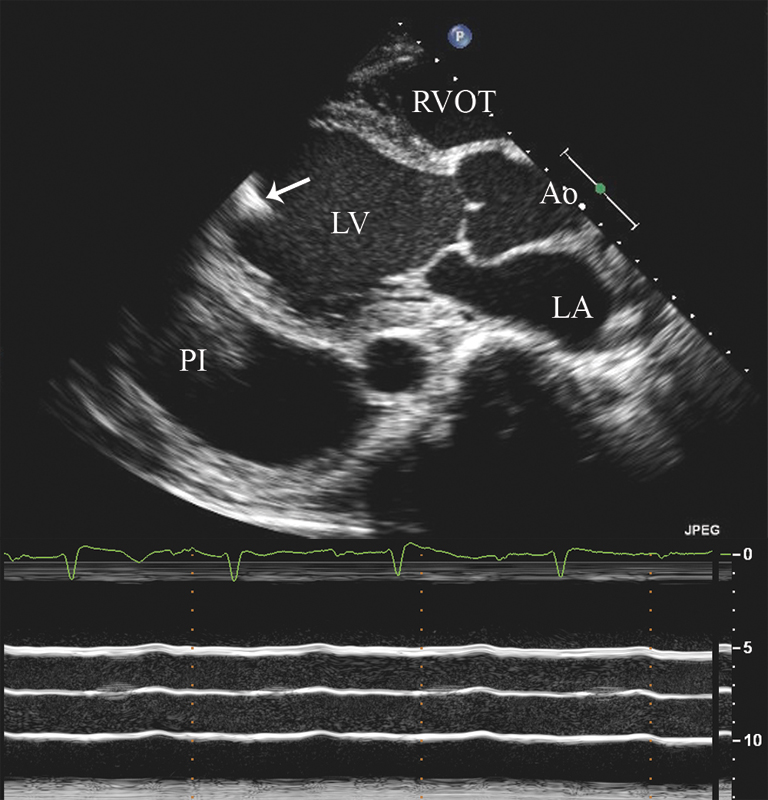

فحوصات تشخيصية لبعض امراض القلب والشرايين التاجية